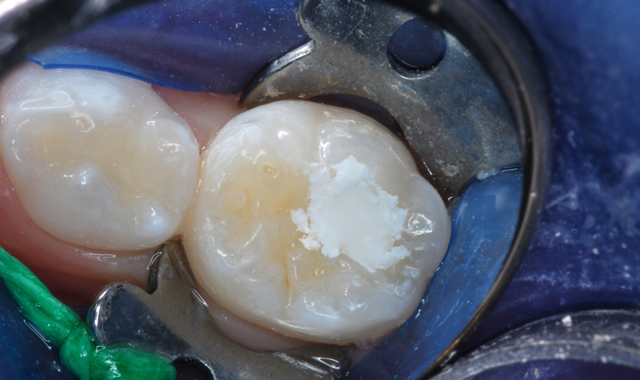

The Aplicap was then placed into the Rotomix™ Capsule Mixing Unit and set for 8 seconds (Fig. 7). The power unit blends the mixture into a putty-like state, ready for injection into the cavity preparation (Fig. 8). After the Aplicap was placed into the injection applicator, the blended Ketac Universal was injected slowly, from the depth of the preparation to overfill (Fig. 9). Care is taken to avoid air entrapment during injection.

Fig. 7 Fig. 8

As soon as injection was completed, the cement was compressed into place with a ball burnisher (Fig. 10). Not only is Ketac Universal non-sticky, but it also has a working time of 110 seconds.

Fig. 9 Fig. 10